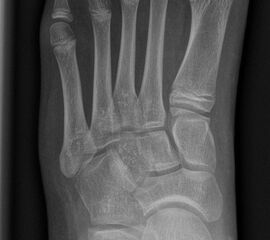

In der Regel bestehen aktive Wachstumsfugen bei Mädchen bis zum 12. und bei Jungen bis zum 14. Lebensjahr, mit Abweichungen von einem Jahr nach unten und nach oben. Präzise Informationen unter anderem darüber gibt das präoperative Röntgenbild (Abb. 2).

Abb. 2 a-c: offene Wachstumsfugen MT I Basis und Zehen (a), teilweise geöffnete Wachstumsfugen (b) und geschlossene Wachstumsfugen (c).

Zum Lesen der Bildbeschreibung und zur Vollansicht bitte die Bilder anklicken. Bilder: A. Helmers.